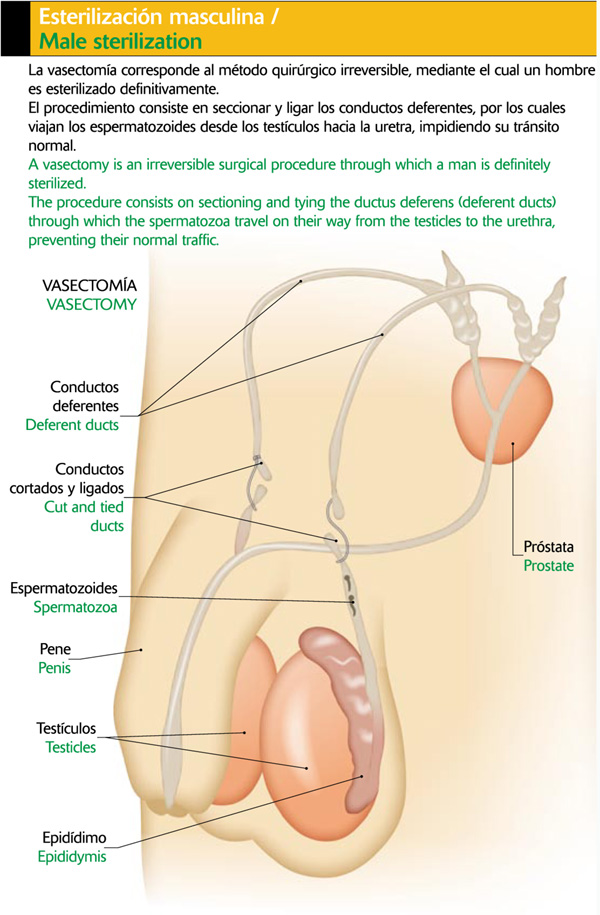

Los conductos deferentes comienzan en la parte inferior de la cola del epidídimo, acompañados de arterias, venas, vasos linfáticos y nervios, formando el cordón espermático que se introduce en la cavidad abdominal. Desembocan en dos dilataciones en forma de bolsa, ubicadas entre la base de la vejiga y el recto: las vesículas seminales. Estas se encargan de elaborar una secreción azucarada que proporciona energía al espermatozoide, y constituye la mayor parte del semen o líquido seminal.

Desde las vesículas seminales surgen los conductos eyaculadores, que desembocan en la uretra a nivel de la próstata. Esta última glándula, del tamaño de una castaña, rodea la uretra en su primera parte. Está formada por dos lóbulos laterales y uno intermedio, y tiene de 10 a 32 unidades glandulares insertas en una masa de tejido muscular liso y conectivo denso.